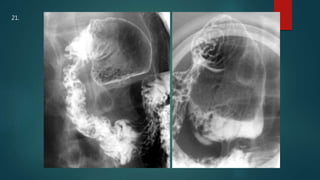

This document appears to be a medical report discussing several patients. It mentions a 35-year-old who was in a severe motor vehicle accident and an 81-year-old with a history of a non-vegetarian diet who had a perforated bowel from a chicken bone. The document provides few other details across its 25 numbered entries and was authored by Dr. Anish Choudhary for junior year 3 on May 30, 2016.